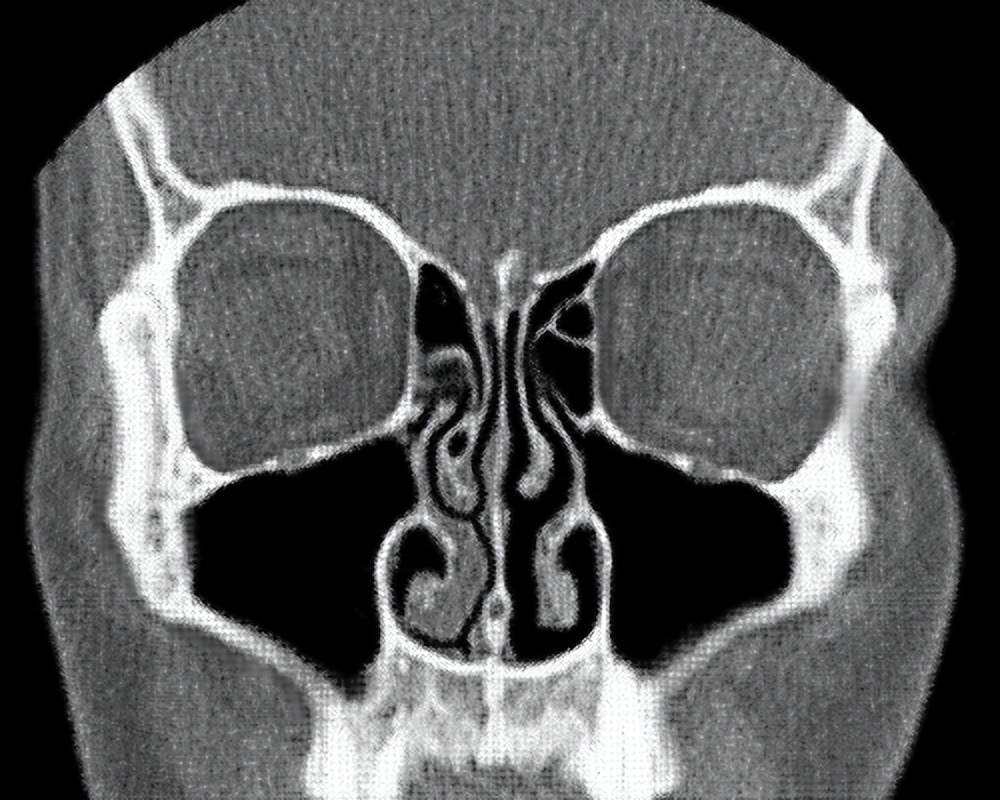

鼻循环

在正常状态下,我们的一个鼻孔处于主要的工作状态来进行呼吸,而另一个鼻孔的呼吸量很少,处于暂时的休息状态。过一段时间另外一只鼻孔开始工作,先前工作的鼻孔则进入休息状态。这种交替工作和休息的过程就叫做 鼻循环 。

也就是说,我们平时吸入和呼出的大部分气体只通过一个鼻孔进出,只有少部分气体会通过另一个鼻孔,因此两个鼻孔总是一侧通一侧相对不通。 事实上,无论是正常还是感冒的状态下,鼻循环都是一直存在的。

鼻循环的时间周期一般为2个小时以上,且随着年龄的增长,循环周期也会逐渐变长,最长的甚至会达到8个小时进行一次循环。我们体内的 植物性神经系统 负责交换两只鼻孔的角色,保证这一交替过程的顺利完成。